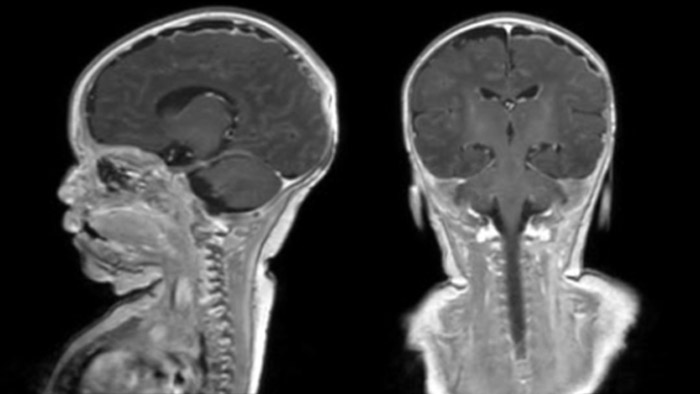

Hydrocephalus post hemorrhagic Both pictures show a ventriculoperitoneal shunt. With our previous scanner our hydrocephalus protocol needed about 25 min. With Ambition the examination time is about 14 min. including a CSF PCA sequence to show flow in the aqueduct.